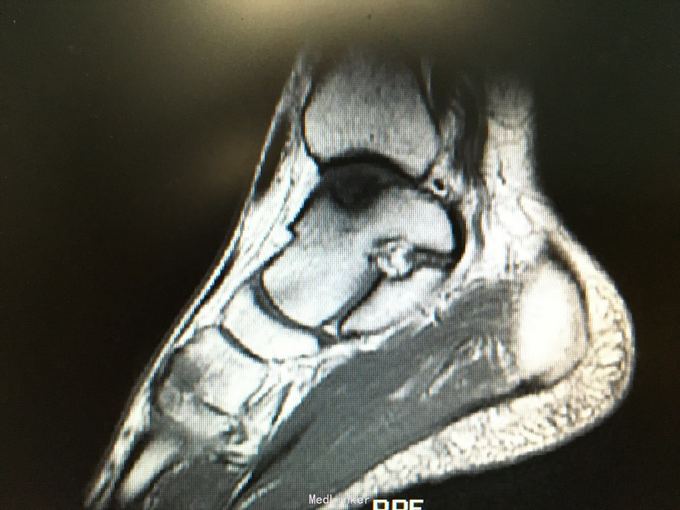

踝关节旋后损伤通常导致距腓前韧带,跟腓韧带以及前外侧关节囊撕裂

查体 辅查 负重时加重,mri示左踝内侧穹隆关节面囊变伴部分坏死

撞击,压迫三角骨,引起踝关节囊后部级相邻的韧带和拇长屈肌腱的炎症